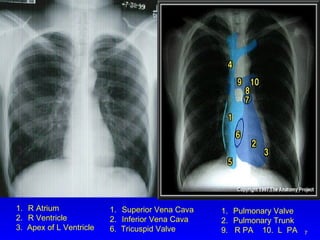

NORMAL HEART BORDERS Note cardiac chambers that account for margins on the chest X-ray

R Atrium R Ventricle 3.  Apex of L Ventricle Superior Vena Cava Inferior Vena Cava 6.  Tricuspid Valve Pulmonary Valve Pulmonary Trunk 9.  R PA  10.  L  PA